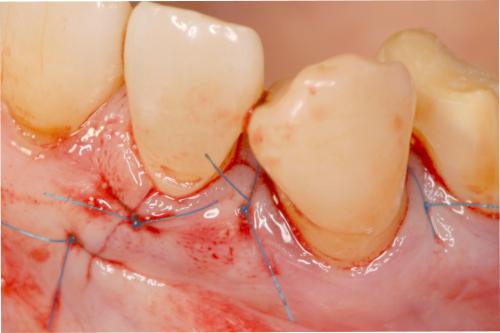

Mikrochirurgischer Wundverschluss

Gingivatransplantat fixiert